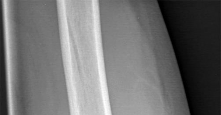

A 3-year-old boy sustains a closed, isolated, midshaft femur fracture after a fall from a playground structure.

Radiographs show 1.5 cm of overriding. What is the most widely accepted definitive management for this patient?

Question 32

An 8-year-old, 35 kg boy sustains a transverse midshaft fracture of the right femur. He is treated with titanium elastic nails (TENs). What is the most common complication associated with this surgical treatment?

Question 47

A 3-year-old boy sustains an isolated midshaft femur fracture. Radiographs demonstrate 1.5 cm of shortening and 10 degrees of varus angulation. What is the most appropriate definitive management?